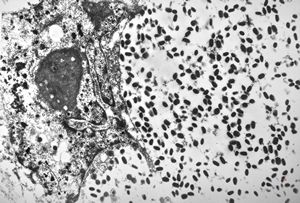

M, 28y. | leishmaniosis … skin of the cheek